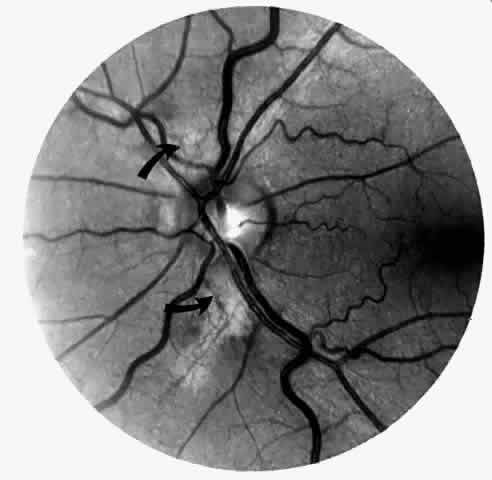

Angioid Streaks

Angioid streaks occur in association with sickle cell disease, with an overall incidence of less than 6%.72–75 The changes are more common in patients with homozygous sickle cell anemia and are age-dependent, occurring in 2% of sickle cell anemia patients less than 40 years of age versus 22% in those who are more than 40 years of age (Fig. 5).76

Fig. 5. A 45-year-old man with homozygous sickle cell anemia and angioid streaks (arrows).

Unlike the angioid streaks seen in patients with pseudoxanthoma elasticum, choroidal neovascularization and disciform disease are uncommon in association with sickle cell disease. Elastic tissue degeneration, as is seen in pseudoxanthoma elasticum, has not been demonstrated in the skin biopsy specimens of sickle hemoglobinopathy patients with angioid streaks.73,75 Initially, the etiology of angioid streaks in sickle cell disease was hypothesized to be secondary to iron deposition due to chronic hemolysis, causing brittleness of Bruch's membrane. Histopathologic examination of angioid streaks in a patient with homozygous sickle cell anemia, however, revealed heavy calcification of Bruch's membrane without evidence of iron or hemosiderin.77